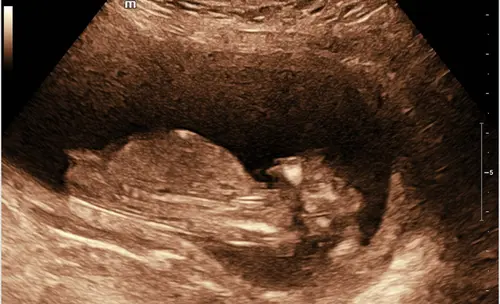

Kan iemand mij helpen bij deze? 14+2 volgende week Officele geslachtsecho maar toch erg nieuwsgierig wat jullie denken hihi:)

Is dit duidelijke een meisje? Door de nub dachten we namelijk eerst een jongen